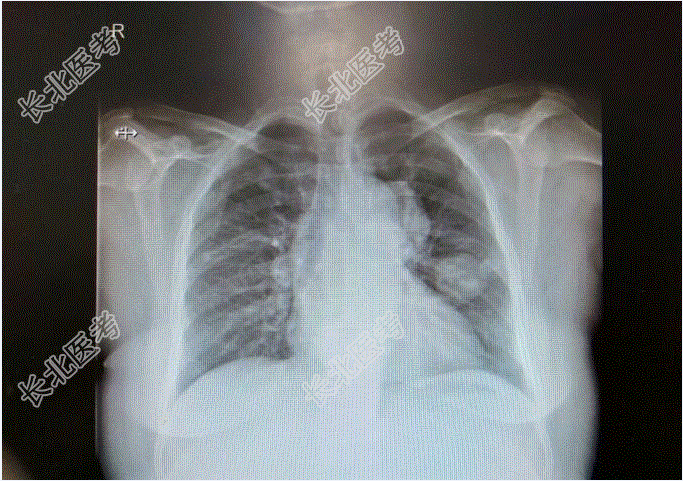

查β-HCG>150000mIU/ml;彩超提示:1、侵袭性葡萄胎待排2、子宫内膜增厚伴宫腔积液3、宫颈肥大伴回声欠均匀4、盆腔积液;2023-1-27外院胸部CT提示:1、两肺多发小结节,考虑转移。再次于行清宫术,术后血HCG下降:160000mIU/ml,术后病理示:镜下见蜕膜、出血、坏死组织中见细胞滋养叶细胞及合体滋养叶细胞。滋养叶细胞增生伴轻度异型,未见确切绒毛结构。患者自诉此次清宫术后血HCG一度下降至50000mIU/ml左右,后复查HCG再次上升至β-HCG:89000mIU/ml。外院会诊后考虑为“绒癌”并于予5Fu1.5静滴8小时d1-8,放线菌素-D0.4mg静滴d1-8化疗。化疗后:β-HCG91000mIU/ml,2023-4-1:β-HCG:90000mIU/ml,2023-4-1外院CT提示胸部多发转移灶较前增大。遂于2017-4-14至我院就诊住院治疗,2023-04-20起给予5-Fu+KSM方案化疗:5-FU(1.5gd1-d4,1.75gd5-d8)+KSM(200μgd1,400μgd2-d8),观察无明显化疗副反应。2023-5-6于外院复查血常规正常,β-HCG2597.36mIU/mL。第二次化疗后至今患者无咳嗽咳痰,恶心呕吐,腹痛腹泻等不适症状。现患者为求进一步诊治,门诊拟“恶性葡萄胎”收治入院。

既往史:患者于25岁时足月顺产一健康活婴;于35岁时足月剖宫产一健康活婴;剖宫产后10月因“葡萄胎”行清宫术3次;2015-02-05再次于外院行清宫术。已婚,2-0-3-2,患者于25岁时足月顺产一健康活婴;于35岁时足月剖宫产一健康活婴。15岁,月经规律,4-5/40,量中,痛经(-),闭经4年。查体:T:36.9℃,P:88次/分,R:18次/分,BP:140/90/mmHg。妇科检查:外阴:(-);阴道:通畅;宫颈:光滑;子宫:前位,增大如孕8周,活动可。双附件(-)。辅助检查:胸片:两肺多个结节影,拟转移瘤,两肺纹理增多,主动脉迂曲。血常规:白细胞计数7.30×10⁹/L,血红蛋白125g/L,血小板计数405↑×10⁹/L。